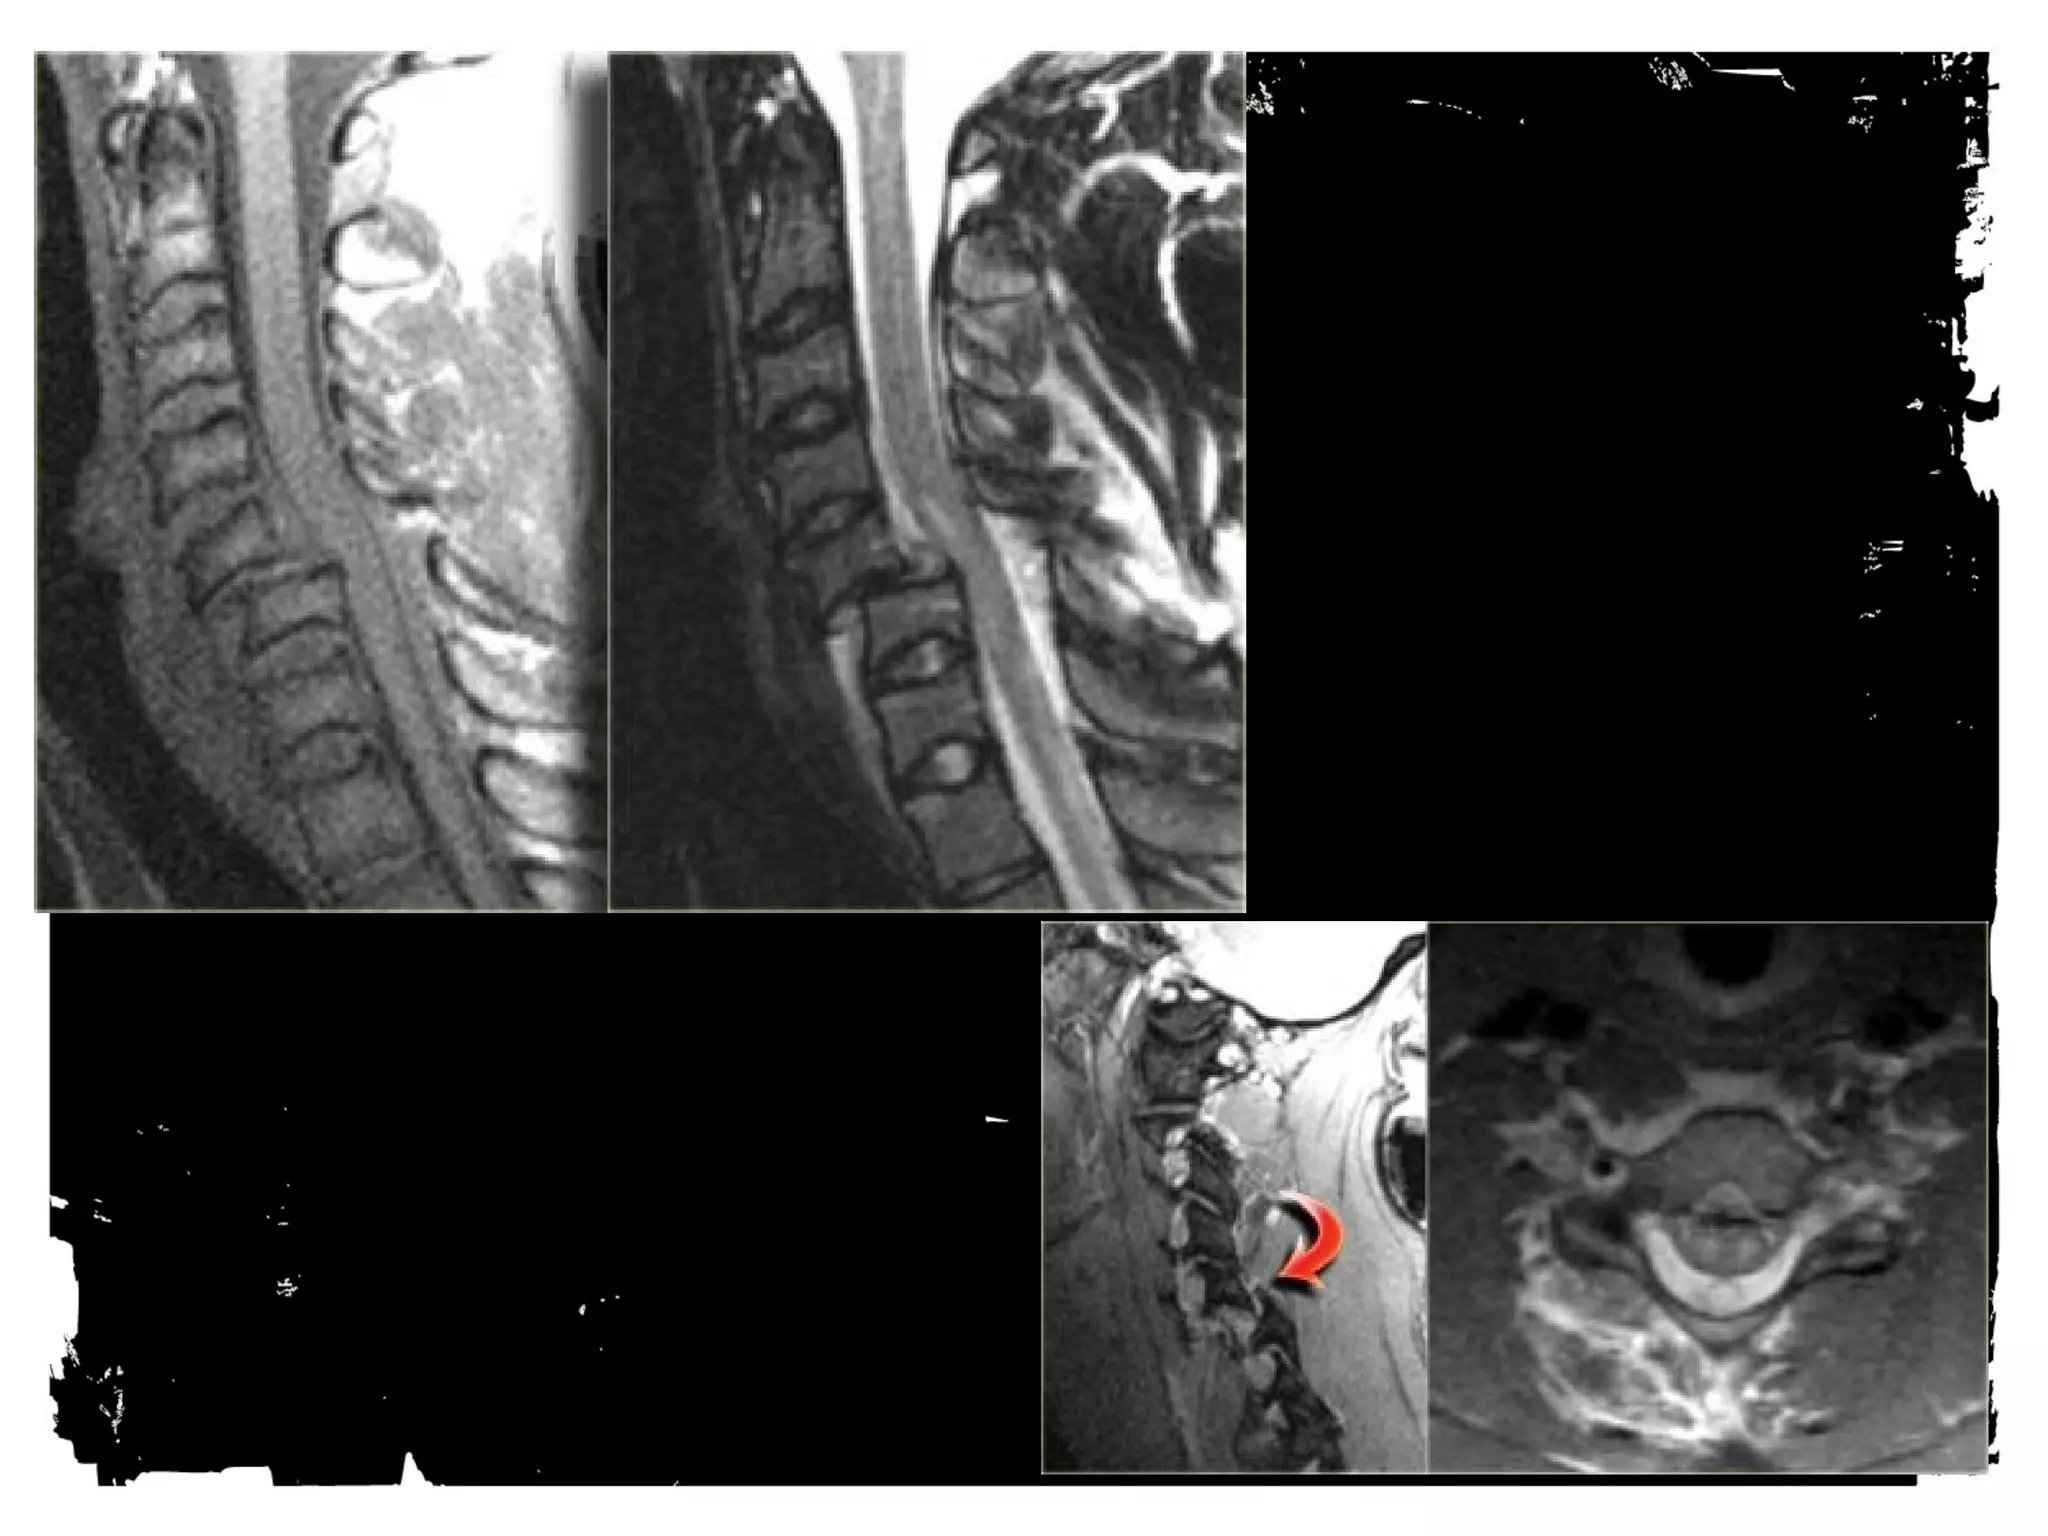

Spinal cord injury (SCI)

Spinal cord injury

There are two types of

injury to the spinal cord:

• Non-hemorrhagic with

only high signal on MR

due to edema.

• Hemorrhagic with areas of

low signal intensity within

the area of edema.

• There is a strong correlation

between the length of the

spinal cord edema and the

clinical outcome.

• The most important factor

however is whether there is

hemorrhage, since

hemorrhagic spinal cord

injury has an extremely poor

outcome.

Midsagittal (a) T1-weighted and (b) T2-weighted MR images obtained in 45-

year-old man with acute traumatic C5 through C6 mild SCI after a fall show

the distances of the spinal canal and spinal cord at the injury site (Di and di,

respectively), one segment below the injury site (Db and db, respectively), and

one segment above the injury site (Da and da, respectively) used to (a)

estimate the MCC and (b) measure spinal canal compression.

©2007 by Radiological Society of North America